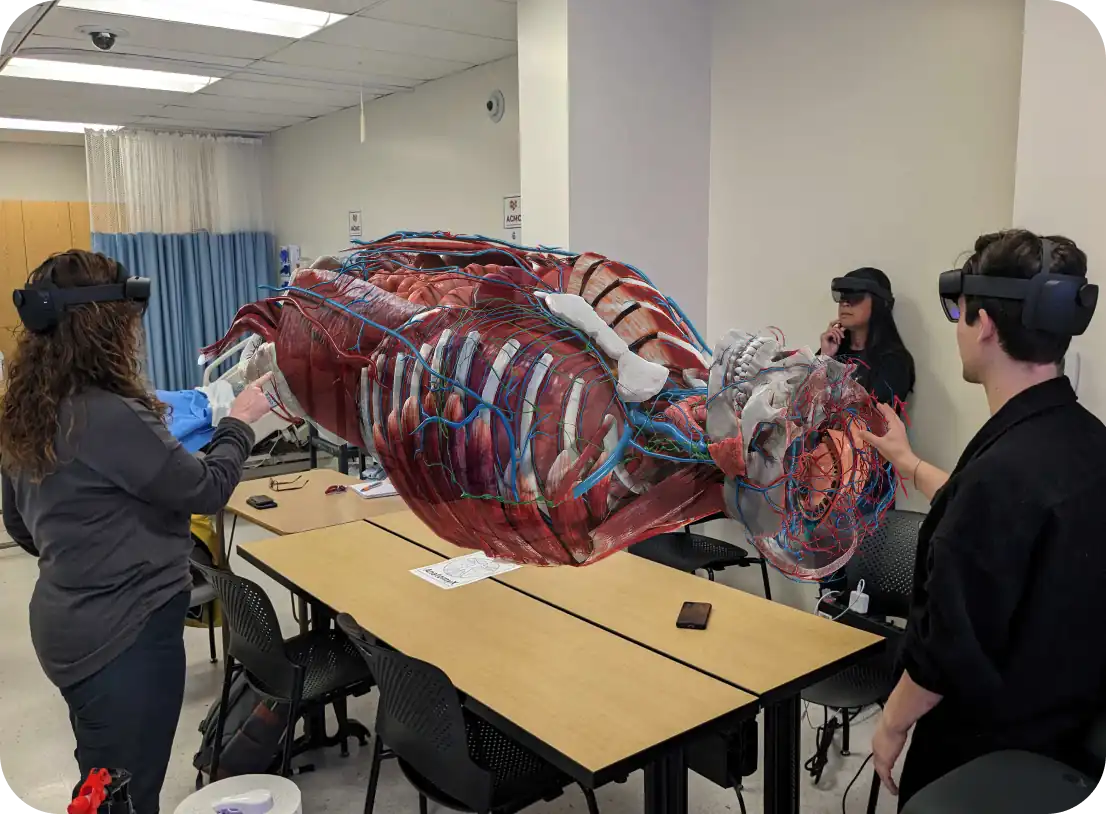

Full-body 3D anatomy education with augmented reality.

A scalable enterprise-level solution for any institution that teaches core anatomy and related health science disciplines. A new, immersive and engaging way to explore the intricacies of the human body—powered by augmented reality.

Microsoft HoloLens 2

Meta Quest 3/3S

Apple Vision Pro

Multi-user shared sessions anywhere.

Multi-user shared sessions across devices.

50+ students supported in a shared session with HoloLens 2, Quest 3/3S, or combination of all.

Multi-user sharing on AnatomyX is a dynamic feature that transforms how users engage with 3D augmented reality for learning anatomy. It allows multiple users to join the same session and interact with the same content in real-time, regardless of their physical location. This innovative approach supports a variety of learning scenarios, from group studies and interactive classes to remote tutoring and collaborative research projects, all designed to enhance learning outcomes, engagement and retention.

AnatomyX can support immersive learning experiences with unlimited simultaneous users in a single sharing session. This capacity is ideal for classroom settings, labs and seminars, allowing for a highly interactive and engaging learning environment where participants can share insights, ask questions and learn from each other in real-time.